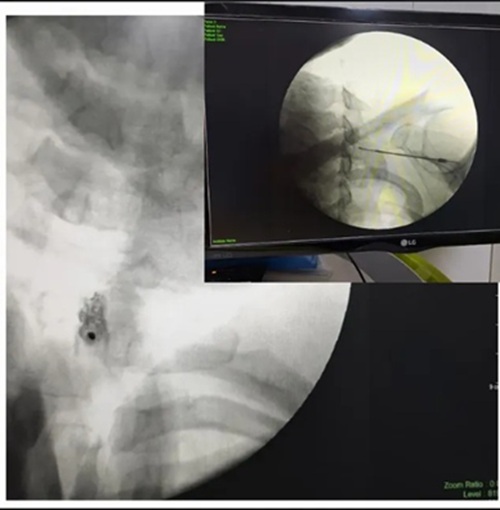

- بلوکهای عصبی تحت هدایت تصویر

- بلاک عصبی تحت فلوروسکوپی